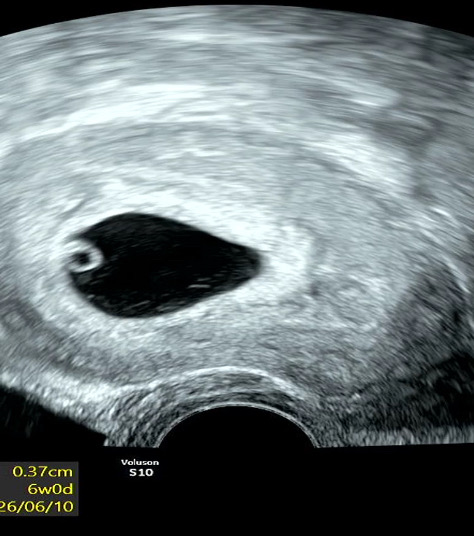

6주0일차 초음파

0.37cm이고, 심박수가 104인데 ㅠㅠ 생각보다 느리게뛴다고 다음주에 다시 진료예약잡았습니다 별일없겠죠 ㅜㅜ.. 심장박동소리들었는데도 기쁘지않고 걱정스러워요 하필 감기도걸려서 앓아누워있어요 ㅠㅠ 다들 감기조심하세요 넘 아프네요 흑흑